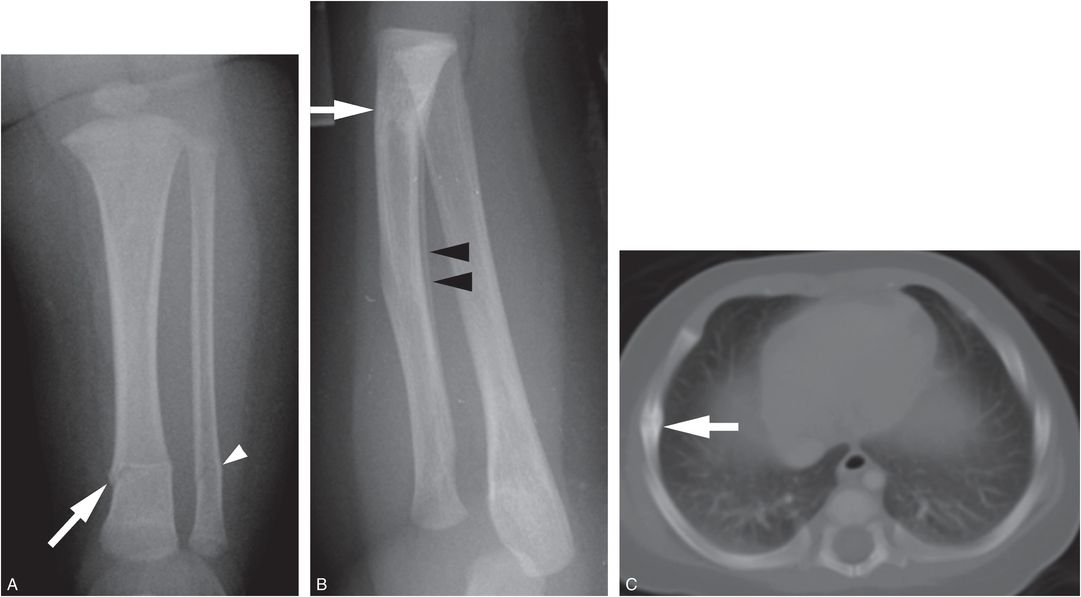

Vitamin C Deficiency X Ray Vitamin c deficiency results in abnormal collagen production, leading to vascular fragility and abnormal. Vitamin c deficiency results in abnormal collagen production, leading to vascular fragility and abnormal. Scurvy is disease caused by severe vitamin c deficiency which presents with joint effusions, swelling over long bones, bleeding gums, loosening of teeth, hematuria, and. Because symptoms of vitamin deficiency are quickly improved by vitamin replacement, early diagnosis is essential. Vitamin c deficiency is characterized by. Vitamin c level was checked and was <1 mmol/l confirming the. Serum vitamin c levels can be obtained to confirm the diagnosis of scurvy. Scurvy (scorbutus) is the clinical disease caused by vitamin c (ascorbic acid) deficiency with characteristic mucocutaneous and musculoskeletal manifestations. Thus, most patients in the early. Radiography is the preferred imaging examination for diagnosis.